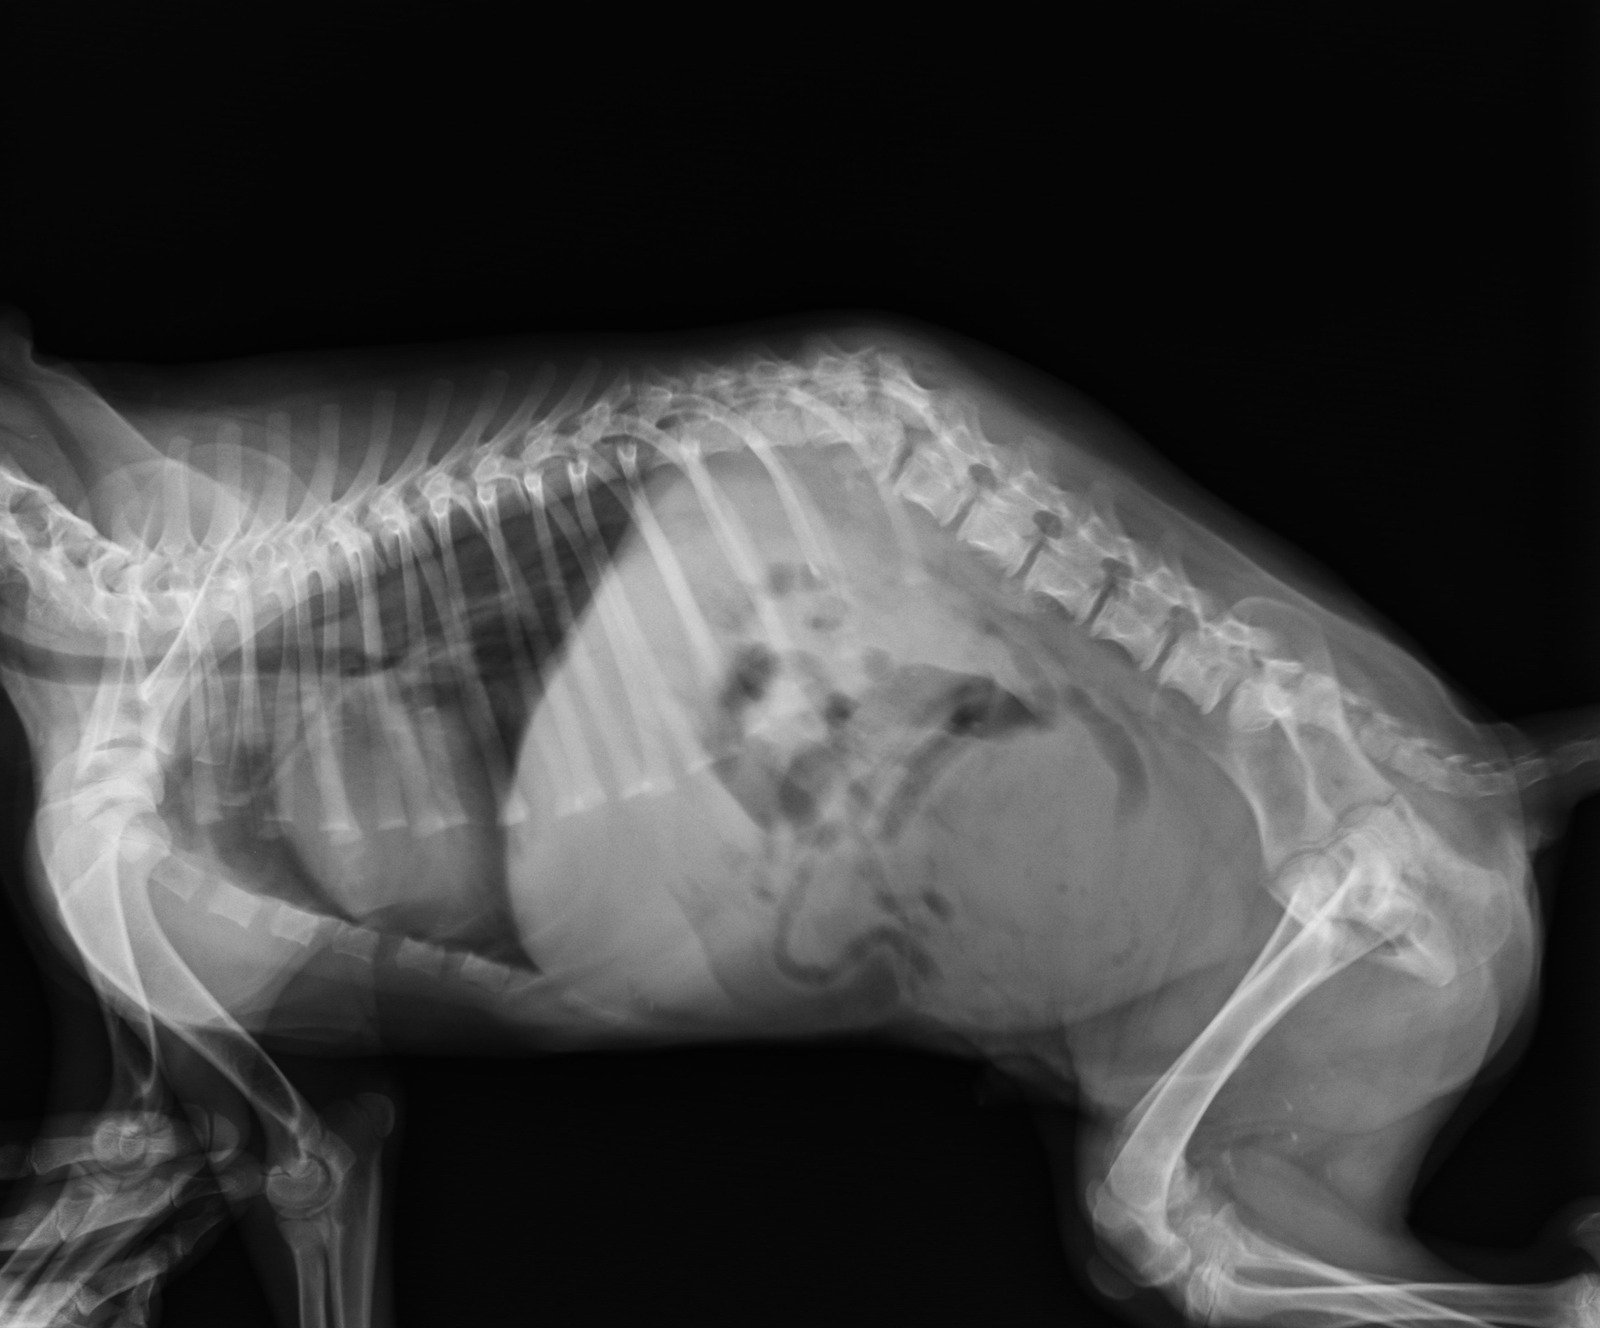

4. 척추 압박 골절 진단 방법

✅ X-ray (척추 X선 검사) → 척추 뼈의 변형 & 골절 여부 확인

✅ CT (전산화 단층 촬영) → 골절의 세부적인 형태 분석

✅ MRI (자기공명영상 검사) → 신경 압박 여부, 급성 vs. 만성 골절 감별

✅ 골밀도 검사 (DXA 스캔) → 골다공증 여부 평가

📌 급성 골절인지, 만성적인 변형인지 감별하는 것이 치료 방향 결정에 중요합니다.